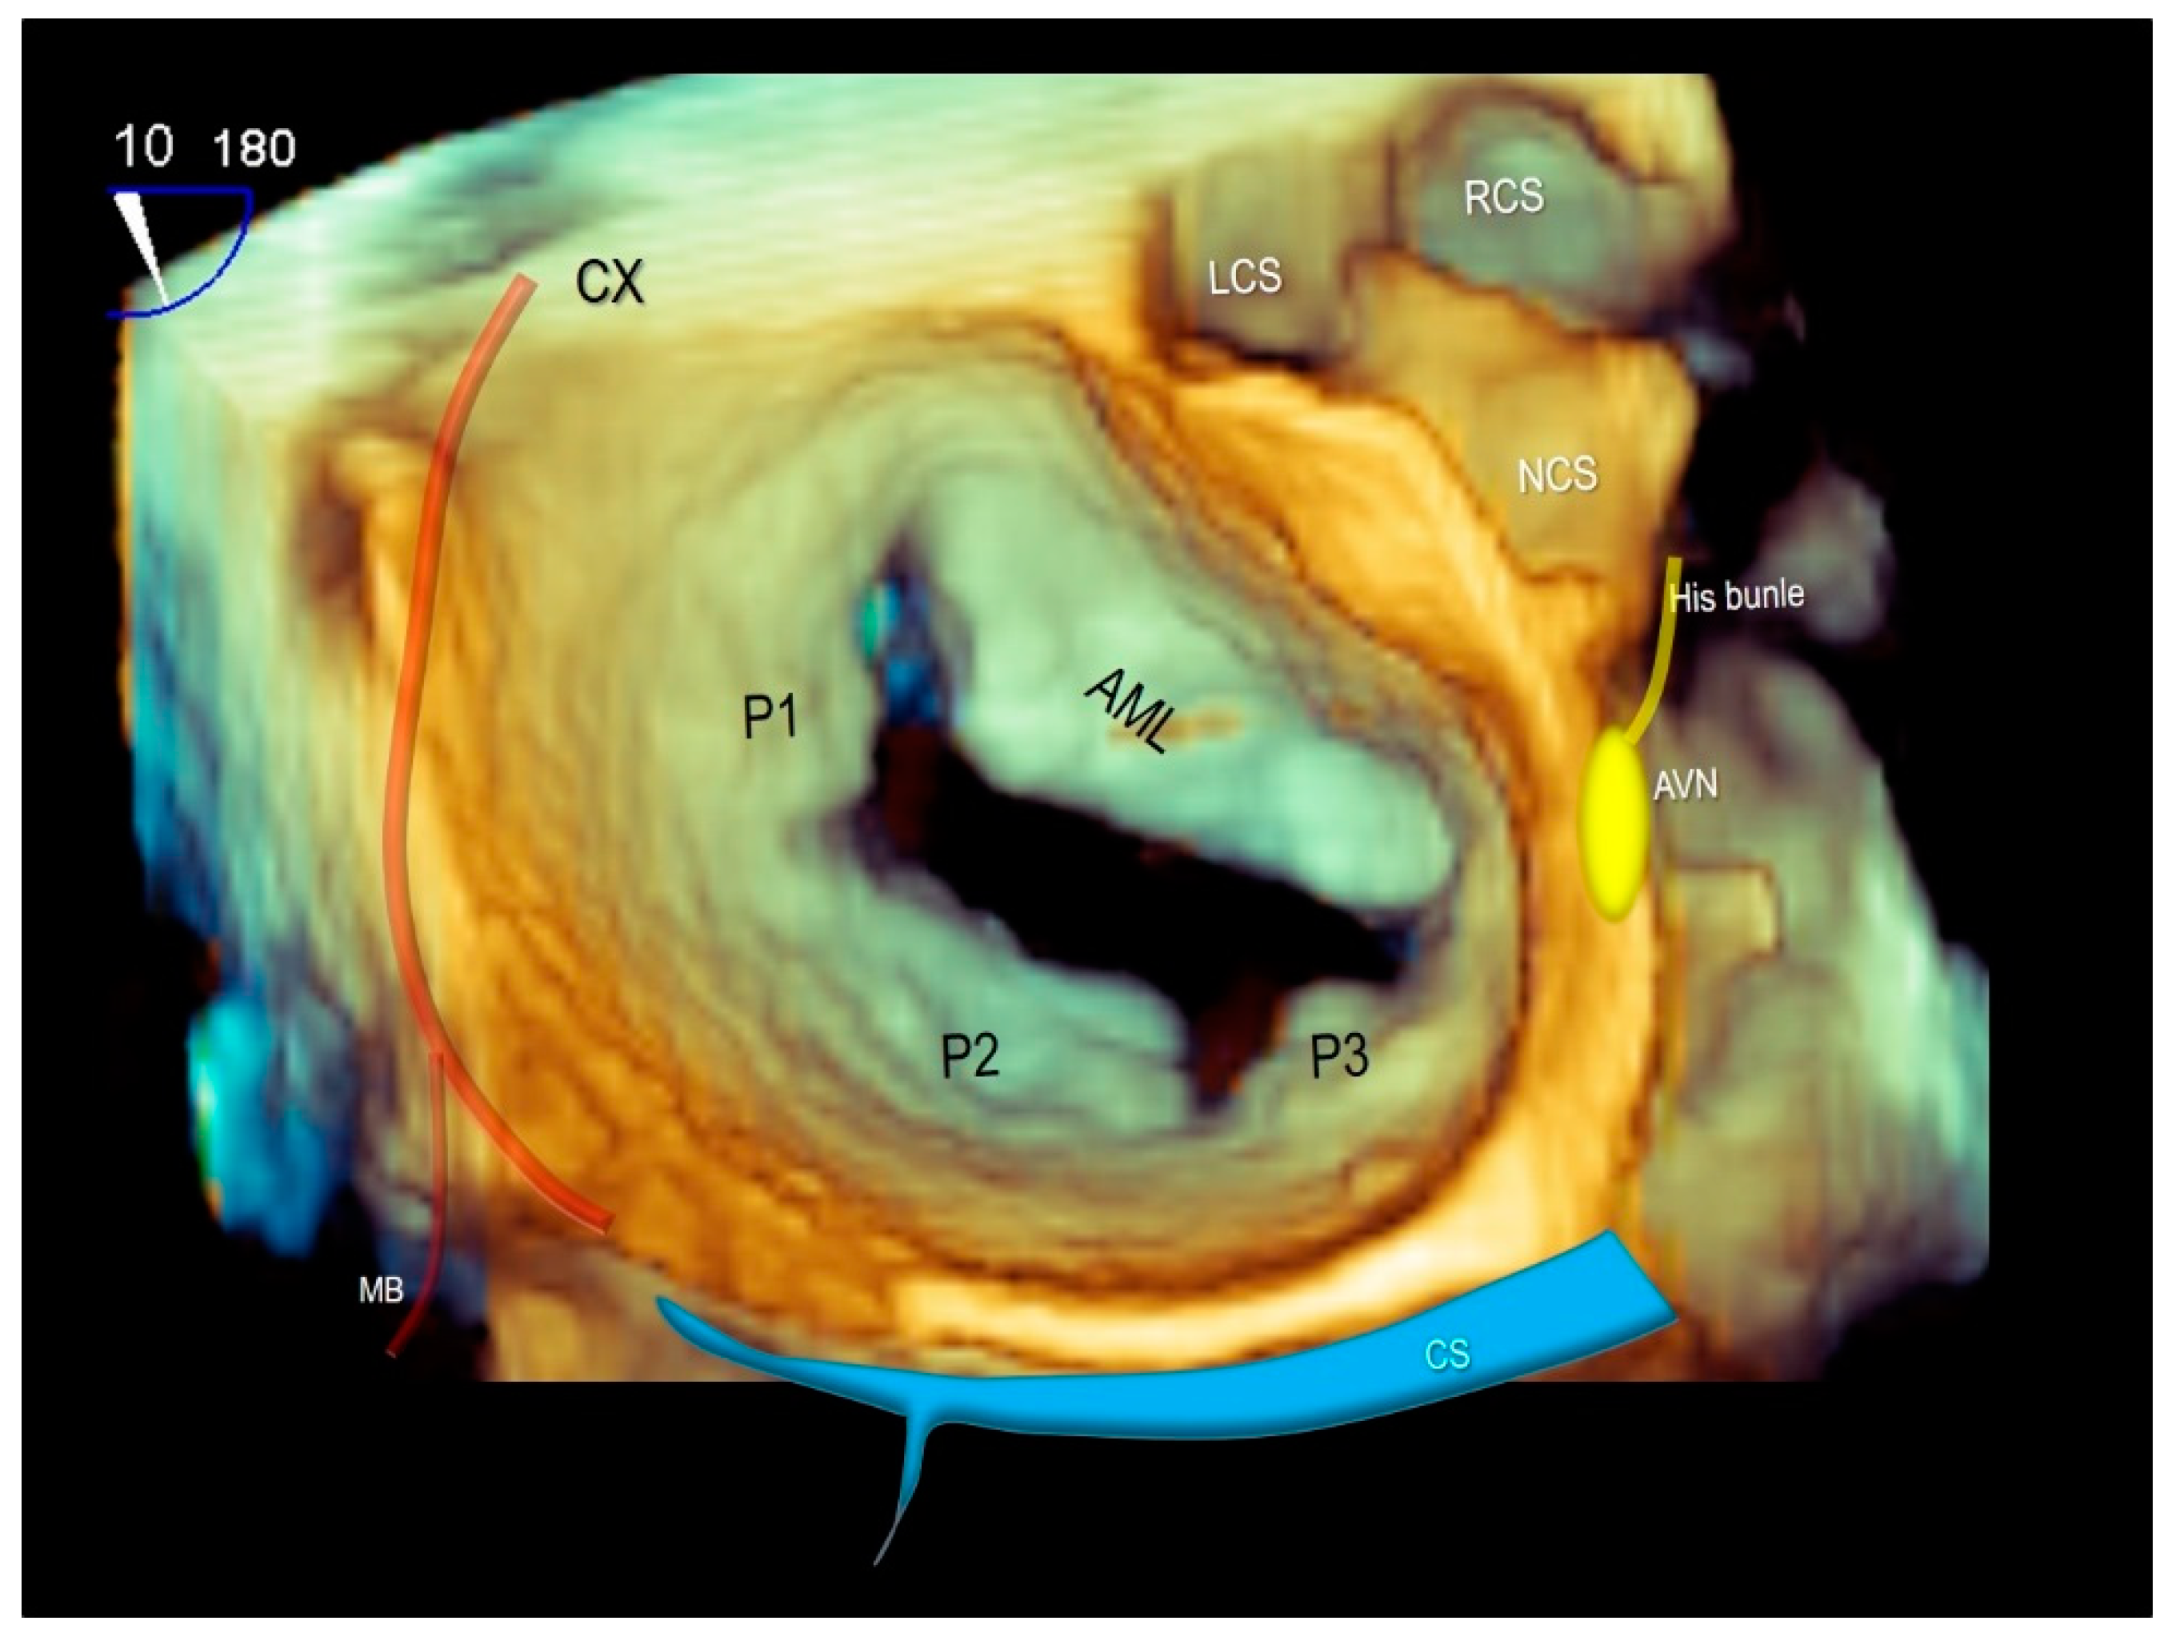

Of note, both the circumflex coronary artery and the coronary sinus are closely related to the posterior mitral valve annulus and can be susceptible to perioperative injury. Furthermore, the atrio-ventricular node is above to the posteromedial commissure of the mitral valve with a potential risk of damage to the atrio-ventricular conduction (Figure 11) [45,46].

Figure 11.

Three-dimensional TEE surgical view of mitral valve showing the anatomical relationships of mitral valve with the circumflex coronary artery (CX), the coronary sinus (CS) and the atrio-ventricular node (AVN). AML = anterior mitral leaflet, P1–P2–P3 = scallops of posterior mitral leaflet, LCS = left coronary sinus, RCS = right coronary sinus, NCS = non-coronary sinus, MB = marginal branch of CX.